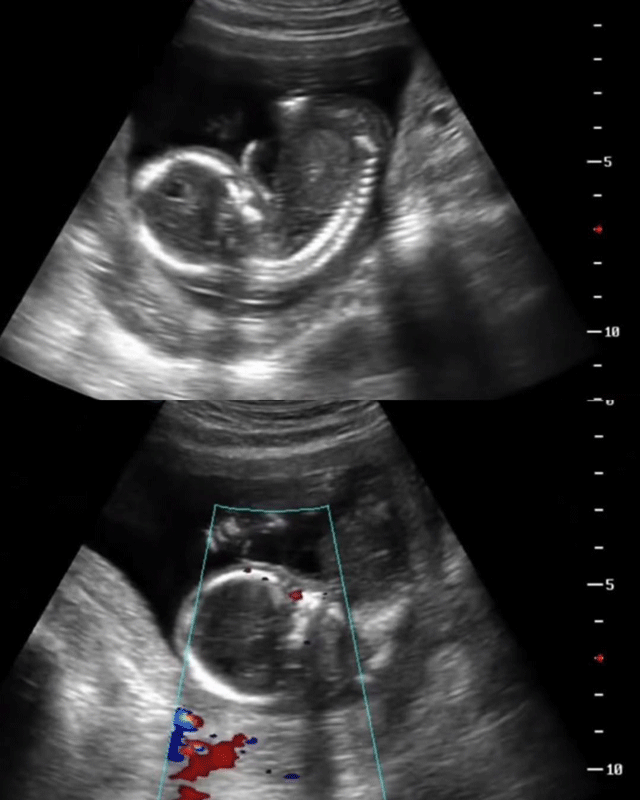

Bác sĩ kể lại câu chuyện thai phụ mất con.

Đến tối cùng ngày, khi nhận thấy thai nhi không còn cử động, chị vội vàng đến phòng khám để kiểm tra. Tuy nhiên, mọi nỗ lực đều trở nên muộn màng. Bác sĩ thông báo chị đã mất tim thai. Đứa con chưa kịp chào đời đã ra đi mãi mãi, để lại nỗi đau không gì bù đắp nổi cho người mẹ.

Ảnh minh họa.